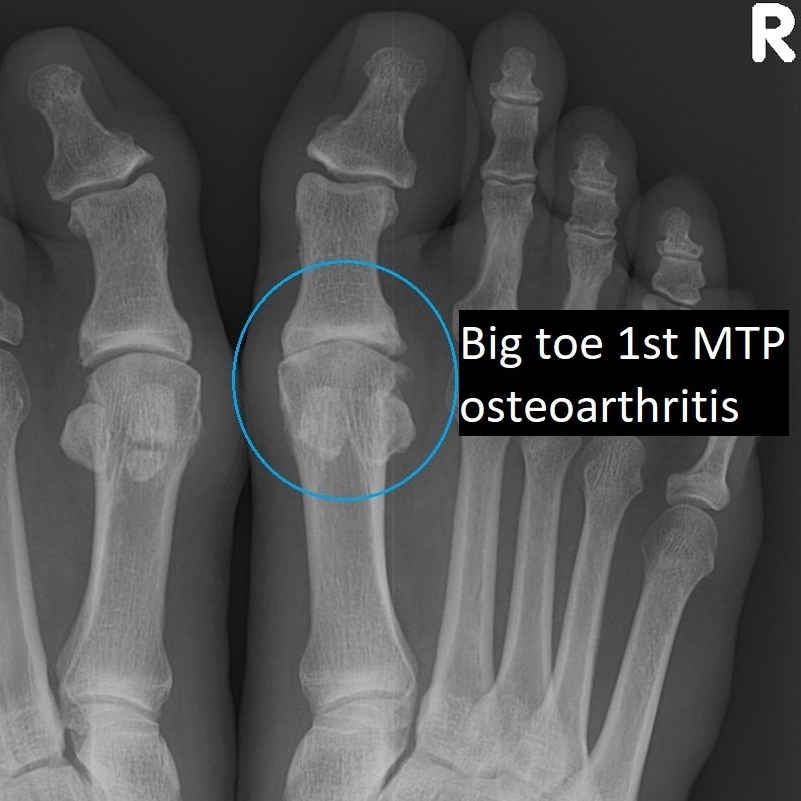

- joint at the base of the big toe (1st metatarsophalangeal/MTP)

Big toe arthritis

can be treated by "clean-out", 1st MTP fusion

and in selected cases only, the Cartiva 1st MTP joint implant.